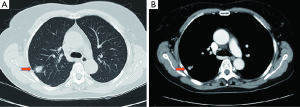

A 64-year-old female presented with a 2.0 cm × 2.0 cm × 1.0 cm nodule in posterior segment of right upper lobe and a ground glass opacity (GGO) in the left upper lobe on computed tomographic (CT) (Figures 1,2) was admitted in our institute on March 16th, 2014. The patient underwent preoperative staging and cardiac and pulmonary function assessment. PET-scan indicates no signs of metastasis. Under general anesthesia with double lumen tube, the patient underwent uniportal cVATS lobectomy for right upper lung tumor on March 19th, 2014 (Figure 3). The final pathologic TNM staging is T1aN0M0 (IA). Regular follow up was initiated for the GGO in the left upper lobe.